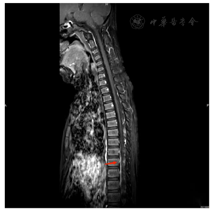

2021年7月16日胸椎MRI:胸7~9椎体水平以下脊髓信号异常,增强后示病灶强化不明显。2021年7月27日胸椎MRI增强(图1)提示胸9~10脊髓及脊髓圆锥内异常信号,出血?2021年8月10日MRI增强(图2)诊断为急性脊髓炎。2021年8月26日MRI增强(图3)提示急性脊髓炎伴脊神经炎,较前有所好转。2021年12月20日胸椎MRI增强(图4)提示急性脊髓炎伴脊神经炎,较2021年8月26日范围稍缩小。

急性脊髓炎。患儿2个月前突发双下肢活动不利、麻木,病变水平以下肢体瘫痪、感觉障碍、尿便障碍。体格检查:神清,精神可,对答切题。颈软,双上肢肌力、肌张力正常,双下肢肌张力低。髂腰肌左侧肌力1+级,右侧肌力1级,余双下肢各关键肌肌力0级。双下肢肌张力低,Ashworth分级:0级。双侧轻触觉:L1水平及以下消失,双侧针刺觉:L1水平及以下消失。腹壁反射(+),膝反射、踝反射消失,病理征阴性。肛门反射(−),球-肛门反射(−)。2021年12月20日胸椎MRI增强:急性脊髓炎伴脊神经炎。故诊断。